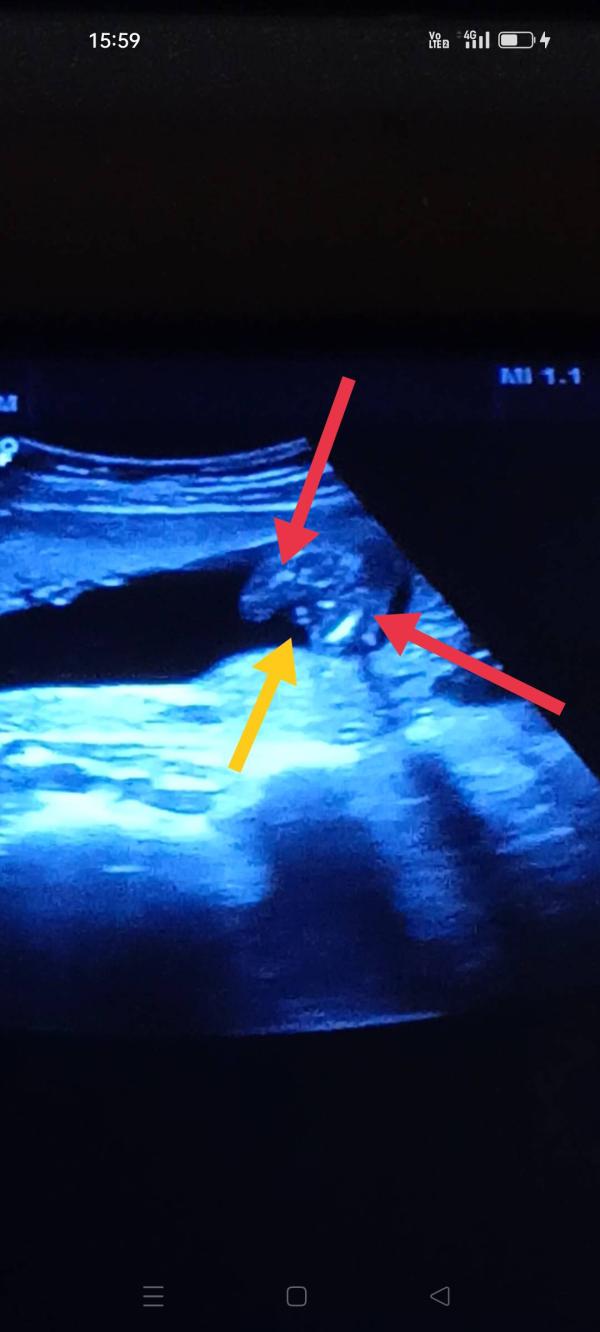

Красными стрелочками это ноги

Жёлтая писюн, так ведь ? 😆ну или яички!

Это УЗИ в 16 недель, а мылаш был почти на 17

Не сказали, она не уверенна, сказала видит на 80% (это было в 16 недель)

Девочка это как раз пирожок где жёлтая стрелочка. Кофейное зёрнышко

Вроде это "кофейное зернышко" 👧👧👧